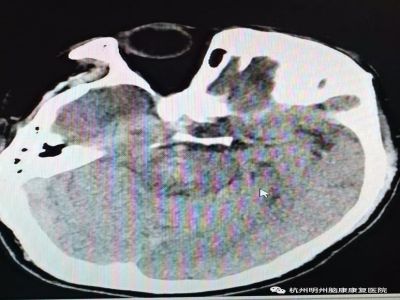

家属立即送其至当地医院,头部和胸部CT提示:脑干出血,左肺肺大疱。随后转入重症监护室接受治疗,期间接受气管切开术。自发病以来,汪先生一直处于昏迷状态。汪先生的家人多方咨询,得到的结论是汪先生成为“植物人”的概率高达80%。

入院评估:脑干出血

即昏迷后第13天,汪先生转入康复医院寻求康复治疗。入院时,汪先生意识不清,瞳孔直接、间接对光反射消失,四肢肌肉萎缩;鼻饲饮食;GCS评分7分(E4V1M2)。

汪先生属于脑干出血偏重型患者,气管切开术后,还患有高血压病、肺部感染、颈动脉斑块、左肺大疱。同时,入院时,汪先生的脑水肿也较为严重。主治医生介绍,脑干水肿或出血破入脑室可引起中脑水管狭窄或阻塞,脑脊液循环不畅形成脑积水,使颅内压进行性升高而加重脑损害。